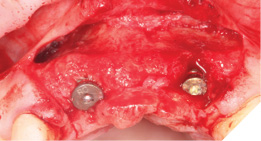

A Papilla sparing extended H-shaped crestal incision was made, full thickness mucoperiosteal flap with clean reflection of the periosteum. The healing alveolar sockets were exposed and used to guide our planned dental implant placements. An initial periosteal release was carried out to allow passive tension free closure (Figs. 10-12).

Fig. 10

Fig. 11

Fig. 12

Straumann Bone Level tapered implants were placed as per the planning above and following the Straumann drill placement protocol. We collected the autogenous bone chips from the flutes of the drills as part of the osteotomy site preparation.

Full Depth Direction Indicators were used to check correct implant angulations for screw retained restorations. The implants were almost wholly within autogenous alveolar bone – however we clearly needed to reinforce and thicken the buccal profile for long-term implant health and gingival stability (Figs. 13-18).